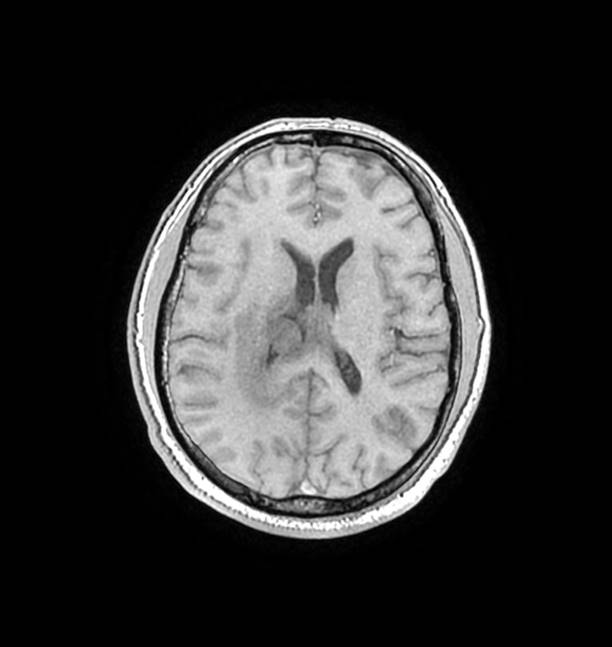

磁共振影像圖

圖1

圖2

圖3

圖4

MR診斷:右側(cè)側(cè)腦室三角區(qū)及側(cè)腦室旁占位,考慮惡性腫瘤可能,間變型腦膜瘤?轉(zhuǎn)移瘤?

MR鑒別診斷

常規(guī)MR檢查是診斷腦膜瘤的有效手段,可以明確腫瘤發(fā)生的部位、形態(tài)和數(shù)目等特征以及病變向鄰近腦實質(zhì)侵犯的程度和范圍,典型腦膜瘤呈等或(和)稍長T1、等或(和)稍長T2信號,??娠@示完整的包膜,增強掃描因腫瘤內(nèi)部新生血管通透性不同呈不同程度強化,由于腫瘤組織的強化程度與腫瘤的惡性程度不完全一致,導致MR常規(guī)檢查在腦膜瘤分級分型方面仍存在一定的困難。擴散加權成像( diffusion weighted imaging,DWI) 及表觀擴散系數(shù)( apparent diffusion coefficient,ADC) 被廣泛用于腦腫瘤的分級、分子分型和腫瘤侵襲性預測,并取得了良好的性能。目前,對于非典型腦膜瘤腦實質(zhì)侵犯的診斷的金標準依賴于組織病理學。